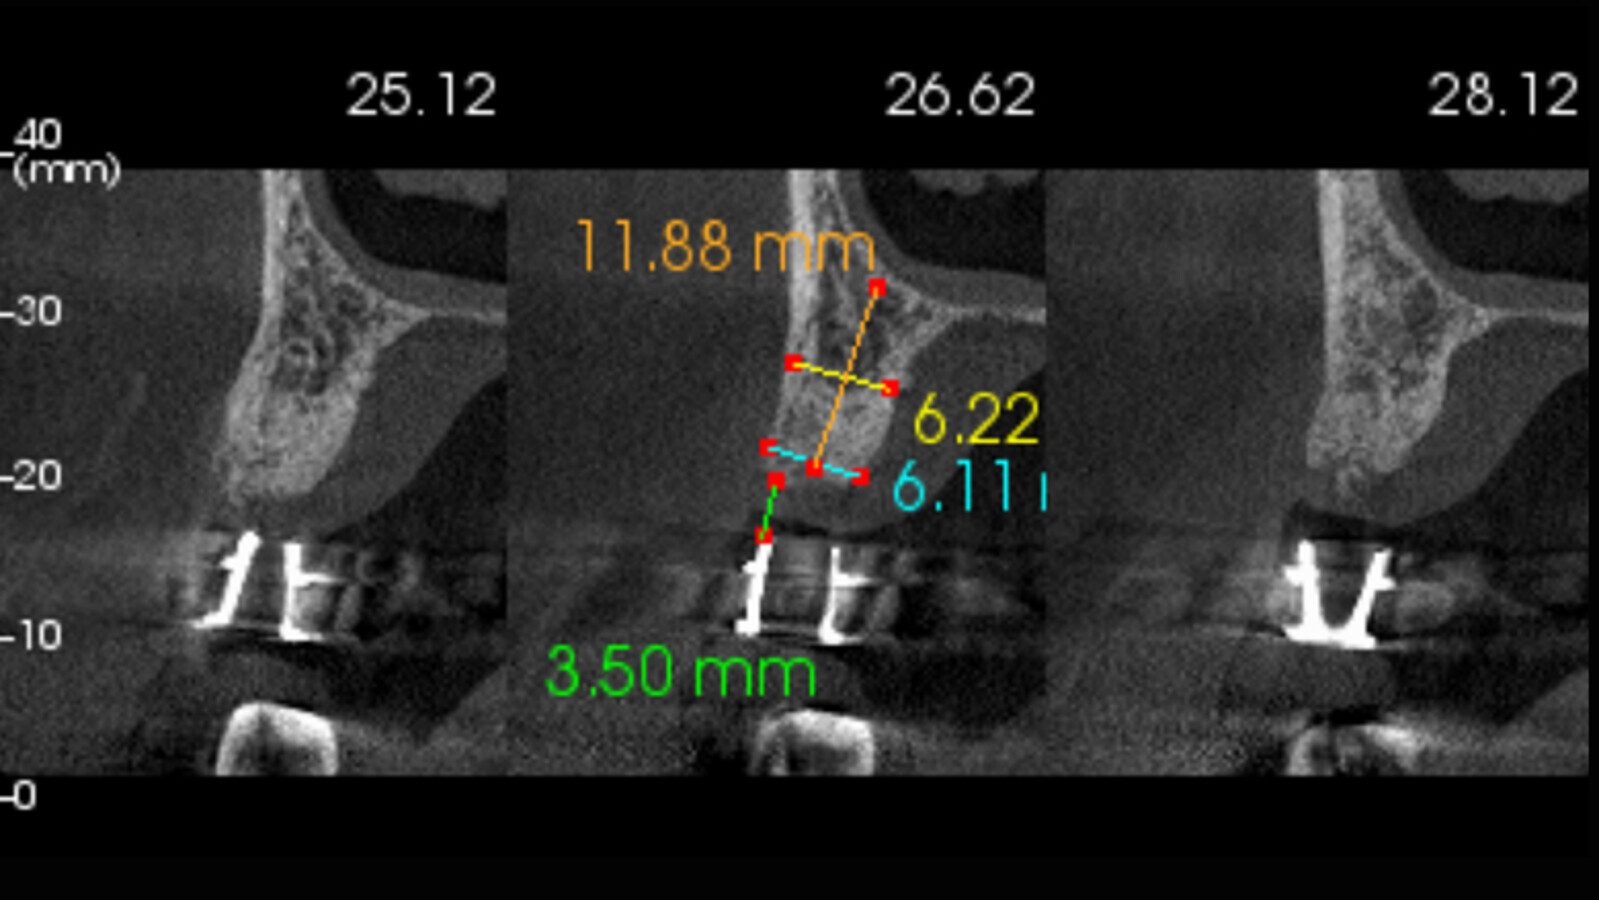

Figura 3. Ya con la tomografía Cone Beam, se procede a medir altura y espesor óseo.